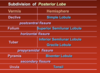

Subdivision of posterior lobe